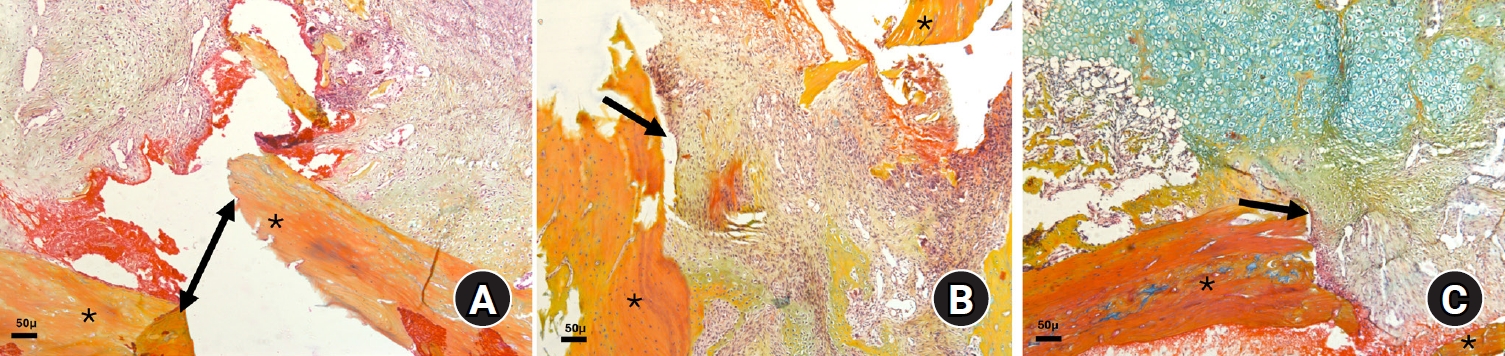

Thirty-six male Wistar (standard outbred) albino rats weighing 200–400 g underwent standardized mid-diaphyseal femoral fracture surgery. The animals were randomized into three groups (n=12 per group): group 1 received diclofenac sodium, group 2 received celecoxib, and group 3 served as the untreated control group received 1 mL distilled water orally once daily. Six rats from each group were euthanized at the end of the 2nd and 7th weeks after fracture for sample collection. Histological examination was complemented by immunohistochemical analysis, and the expression of type X collagen and vascular endothelial growth factor (VEGF) was assessed using the immunoreactive score (IRS) method.

Healing scores were significantly higher in the control group at both time points (2nd week, P=0.01; 7th week, P=0.03). At the 2nd week, rats treated with diclofenac sodium demonstrated significantly greater fibrosis (P=0.01), and by the 7th week, they exhibited impaired bone formation (P=0.003) along with increased bone defects (P=0.01). IRS values for type X collagen and VEGF were significantly higher in the control group than in both treatment groups during the 2nd week (P=0.01 and P=0.005, respectively).

These findings suggest that, in this rat model, NSAIDs, particularly nonselective COX inhibitors, may disrupt the early phases of bone repair by affecting hypertrophic chondrocyte differentiation and reducing angiogenic activity. Although these results indicate a potential risk to optimal healing, they are preclinical observations, and their relevance to clinical fracture management should be interpreted with caution.